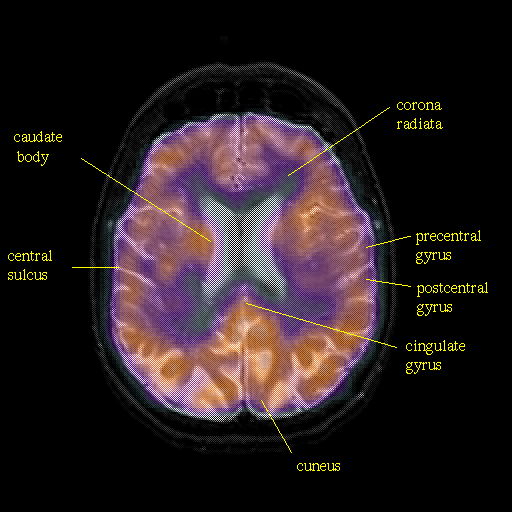

Pointers

Labeled